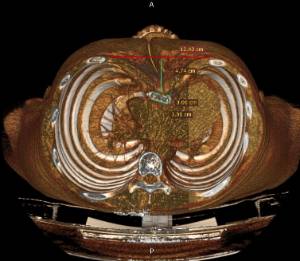

Les dades mèdiques del pacient, més l'exploració clínica realitzada per l'equip de cirurgia, juntament amb una anàlisi detallada de les imatges del TAC i les reconstruccions digitals en 3D de cada tòrax realitzades conjuntament amb l'equip d'enginyers de Ventura Medical Technologies, són la base per determinar si la tècnica Pectus Up està indicada i com cal procedir en cadascun dels pacients.

Amb aquestes dades se selecciona l'implant que millor s'ajusta a l'anatomia de cada tòrax, la ubicació exacta del sistema d'elevació i, alhora, proporciona a l'equip quirúrgic un detall dels passos que cal tenir en compte per fer-ne una correcta implantació.

Pectus Excavatum Pectus Excavatum Asimétrico Índice de Asimetría 0.6 (+R/-L)(|AI|> 0.05 Asimétrico) Índice de Haller 4.5 (HI >3.5) Índice de Corrección 49.13% Rotación esternal 18.1 ° (a la derecha)

Informe d'avaluació del TAC d'un pacient enviada al cirurgià